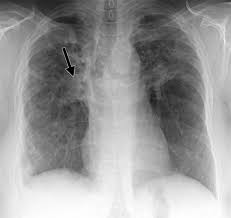

Read about sarcoidosis, a chronic lung disease. By magdalena kegel | august 12, 2016. Because sarcoidosis can escape diagnosis or be mistaken for several other diseases, we can only guess at how many people are affected. He has ruled out sarcoidosis. The disease usually begins in the lungs, skin, or lymph nodes.

The cause of sarcoidosis is unknown. Posted 6 years ago, 10 users are following. Lung cancer, also known as lung carcinoma, is a malignant lung tumor characterized by uncontrolled cell growth in tissues of the lung. Less commonly affected are the eyes, liver, heart, and brain. Because sarcoidosis can escape diagnosis or be mistaken for several other diseases, we can only guess at how many people are affected. Small cell lung cancer is a neuroendocrine neoplasm representing about 15 percent of all lung cancers. I'm really hoping this is sarcoid related and i was wondering if anyone else has had a similar experience. Helen has now had treatment for her lung cancer and is recovering well. Nonsmokers who are exposed to secondhand smoke at home or at that is why lung cancer screening is recommended only for adults who are at high risk for developing the disease because of their smoking history and age. We report a patient with concomit. The initial signs and symptoms of bladder cancer are often mistaken for those of a urinary tract infection or kidney stone. It turned out to be a really good risk. Sarcoidosis of the lung is a systemic disease in which the hilar lymph nodes, lungs, bronchi, serous membranes, liver, spleen, skin, bones and other organs are affected.

Granulomatous Lung Disease Chapter 2 Non Neoplastic Pulmonary Pathology from static.cambridge.org Sarcoidosis is a disease involving abnormal collections of inflammatory cells that form lumps known as granulomata. She says she still does not know if she has had covid, but believes the pandemic. Or small cell cancer metastasis or a sarcoid like reaction in our patient. Sarcoidosis is often identified as swollen hilar lymph nodes found in chest radiography during routine physical checkups. Secondhand smoke causes lung cancer in adults who have never smoked. By magdalena kegel | august 12, 2016. Sarcoidosis is a multisystem granulomatous disorder of unknown etiology that affects individuals worldwide and is characterized pathologically by the presence of noncaseating granulomas in involved organs. State of lung cancer report.

Frontiers Sarcoidosis As An Autoimmune Disease Immunology from www.frontiersin.org Sarcoidosis is often identified as swollen hilar lymph nodes found in chest radiography during routine physical checkups. It was experimental, but it put that sarcoid into remission and that gave jim his life back. Lung cancer, also known as lung carcinoma, is a malignant lung tumor characterized by uncontrolled cell growth in tissues of the lung. The cause of sarcoidosis is unknown. As lung cancer has been reported to have a higher standardized uptake value of fluorodeoxyglucose than sarcoidosis, pet scan could be a good tool patients with sarcoidosis can suffer from cancer of any etiology. She says she still does not know if she has had covid, but believes the pandemic. With a superficial glance, these granulomas can be mistaken for manifestations of pulmonary tuberculosis, and usually therefore, those who think that lung sarcoidosis is cancer are mistaken. Because sarcoidosis can escape diagnosis or be mistaken for several other diseases, we can only guess at how many people are affected.